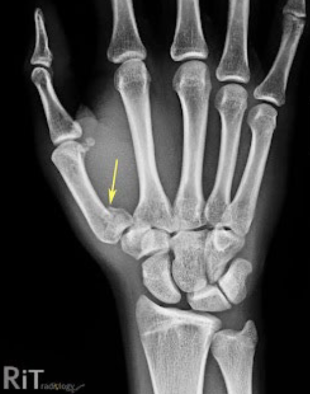

What is this fracture?

Boxer

What is boxer fracture?

Fracture of distal fifth metacarpal

Results from punching someone or something